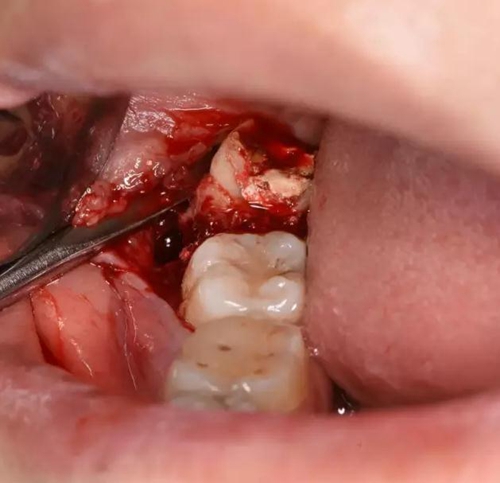

圖9.然后頰側(cè)用挺、挺出48牙齒

圖10.牙齒脫穎而出,48雙根、牙根較大。